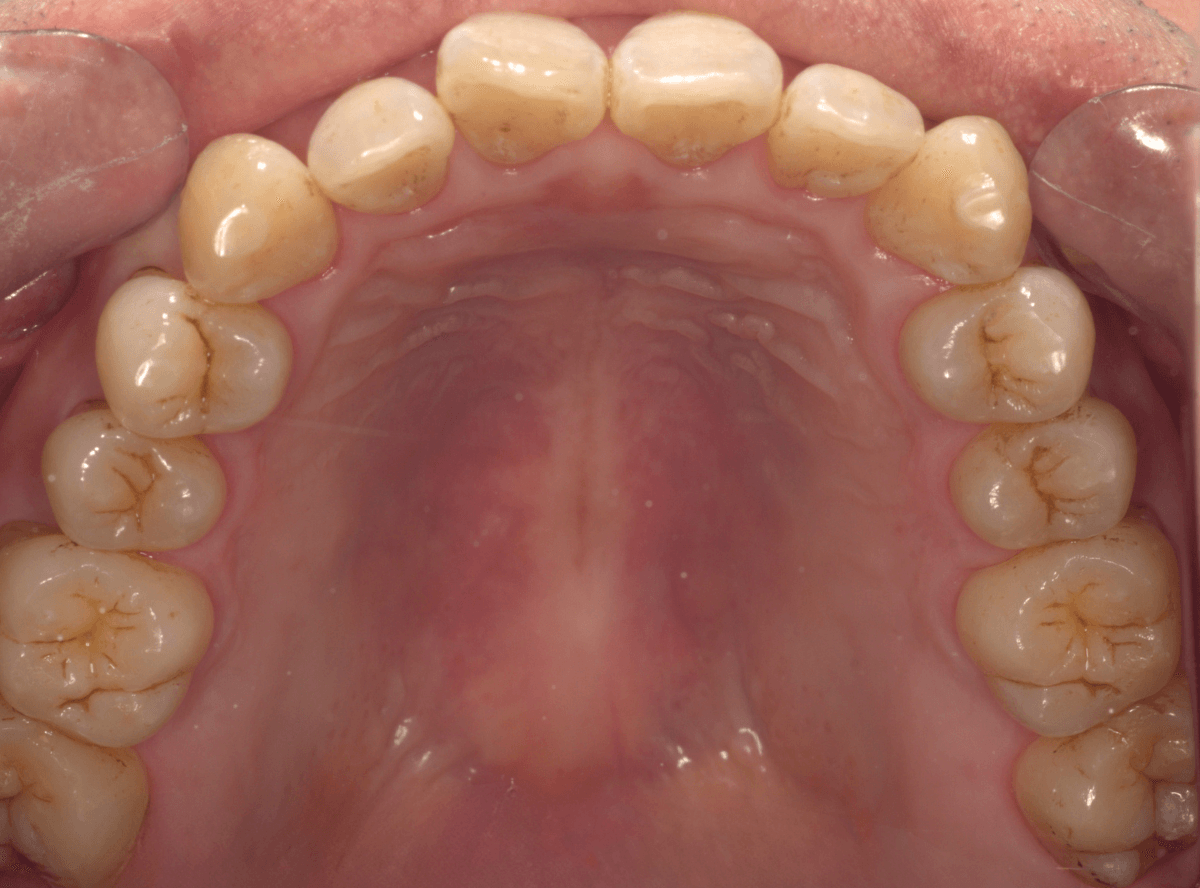

60分かけて、歯をクリーニング・仕上げにコーティングをしました。

着色をしっかり除去するのは意外と時間がかかります。お風呂の掃除をイメージしてもらうといいかもしれません。

着色が残っている部分は、歯ではなく虫歯の治療後につめるレジンが変色しているからです。

こちらを綺麗にする場合は、別途レジンのつめ直しが必要です。